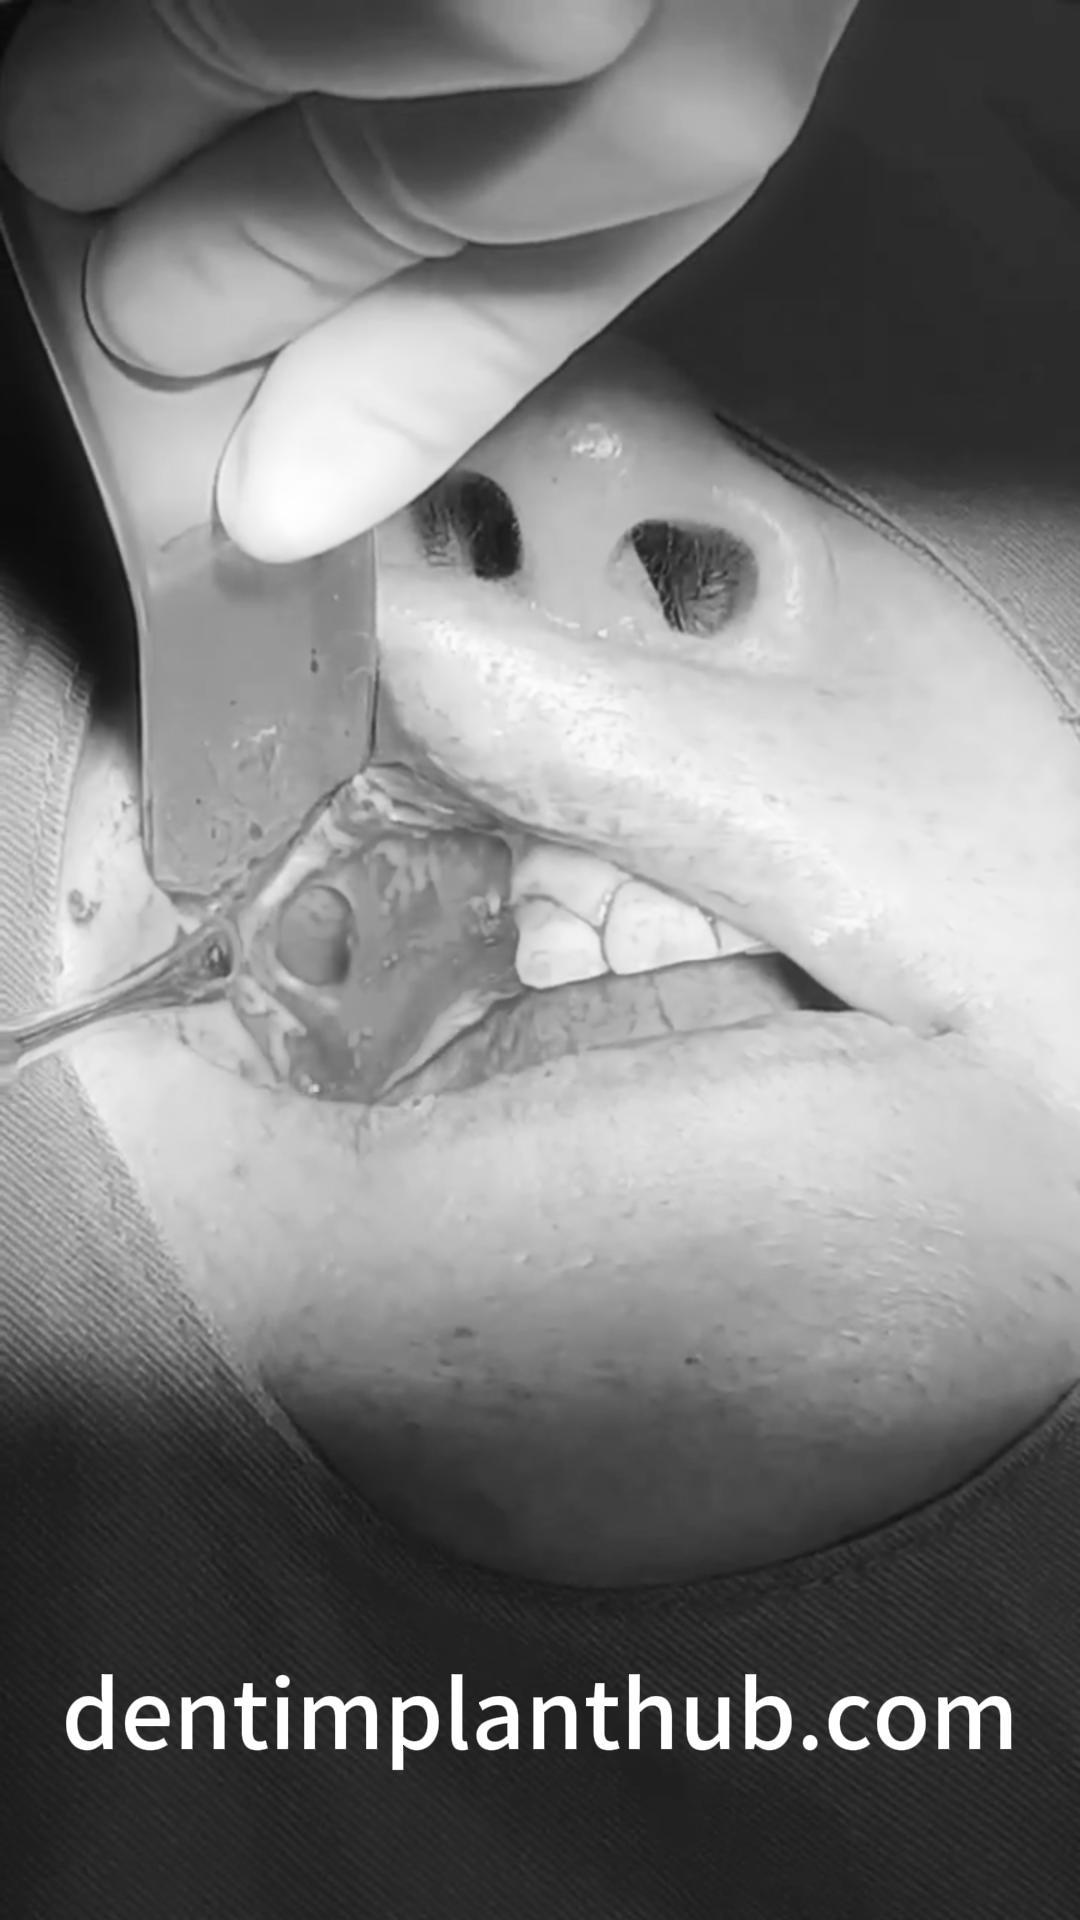

Case 4: Bilateral maxillary sinus lateral wall openings